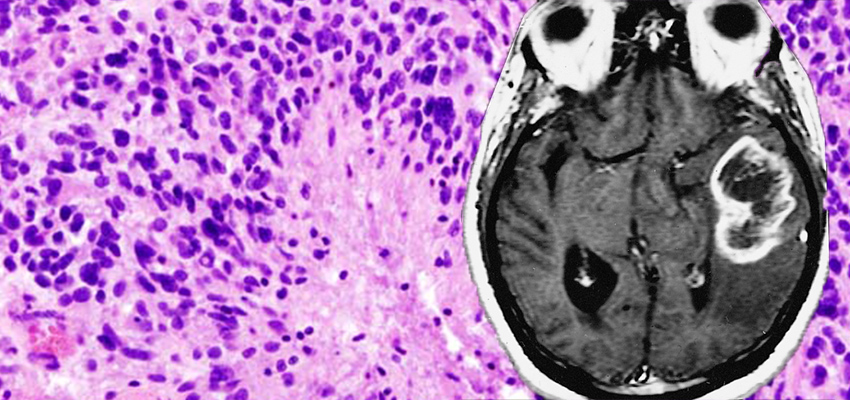

Микрофотографии гистологии глиобластомы головного мозга